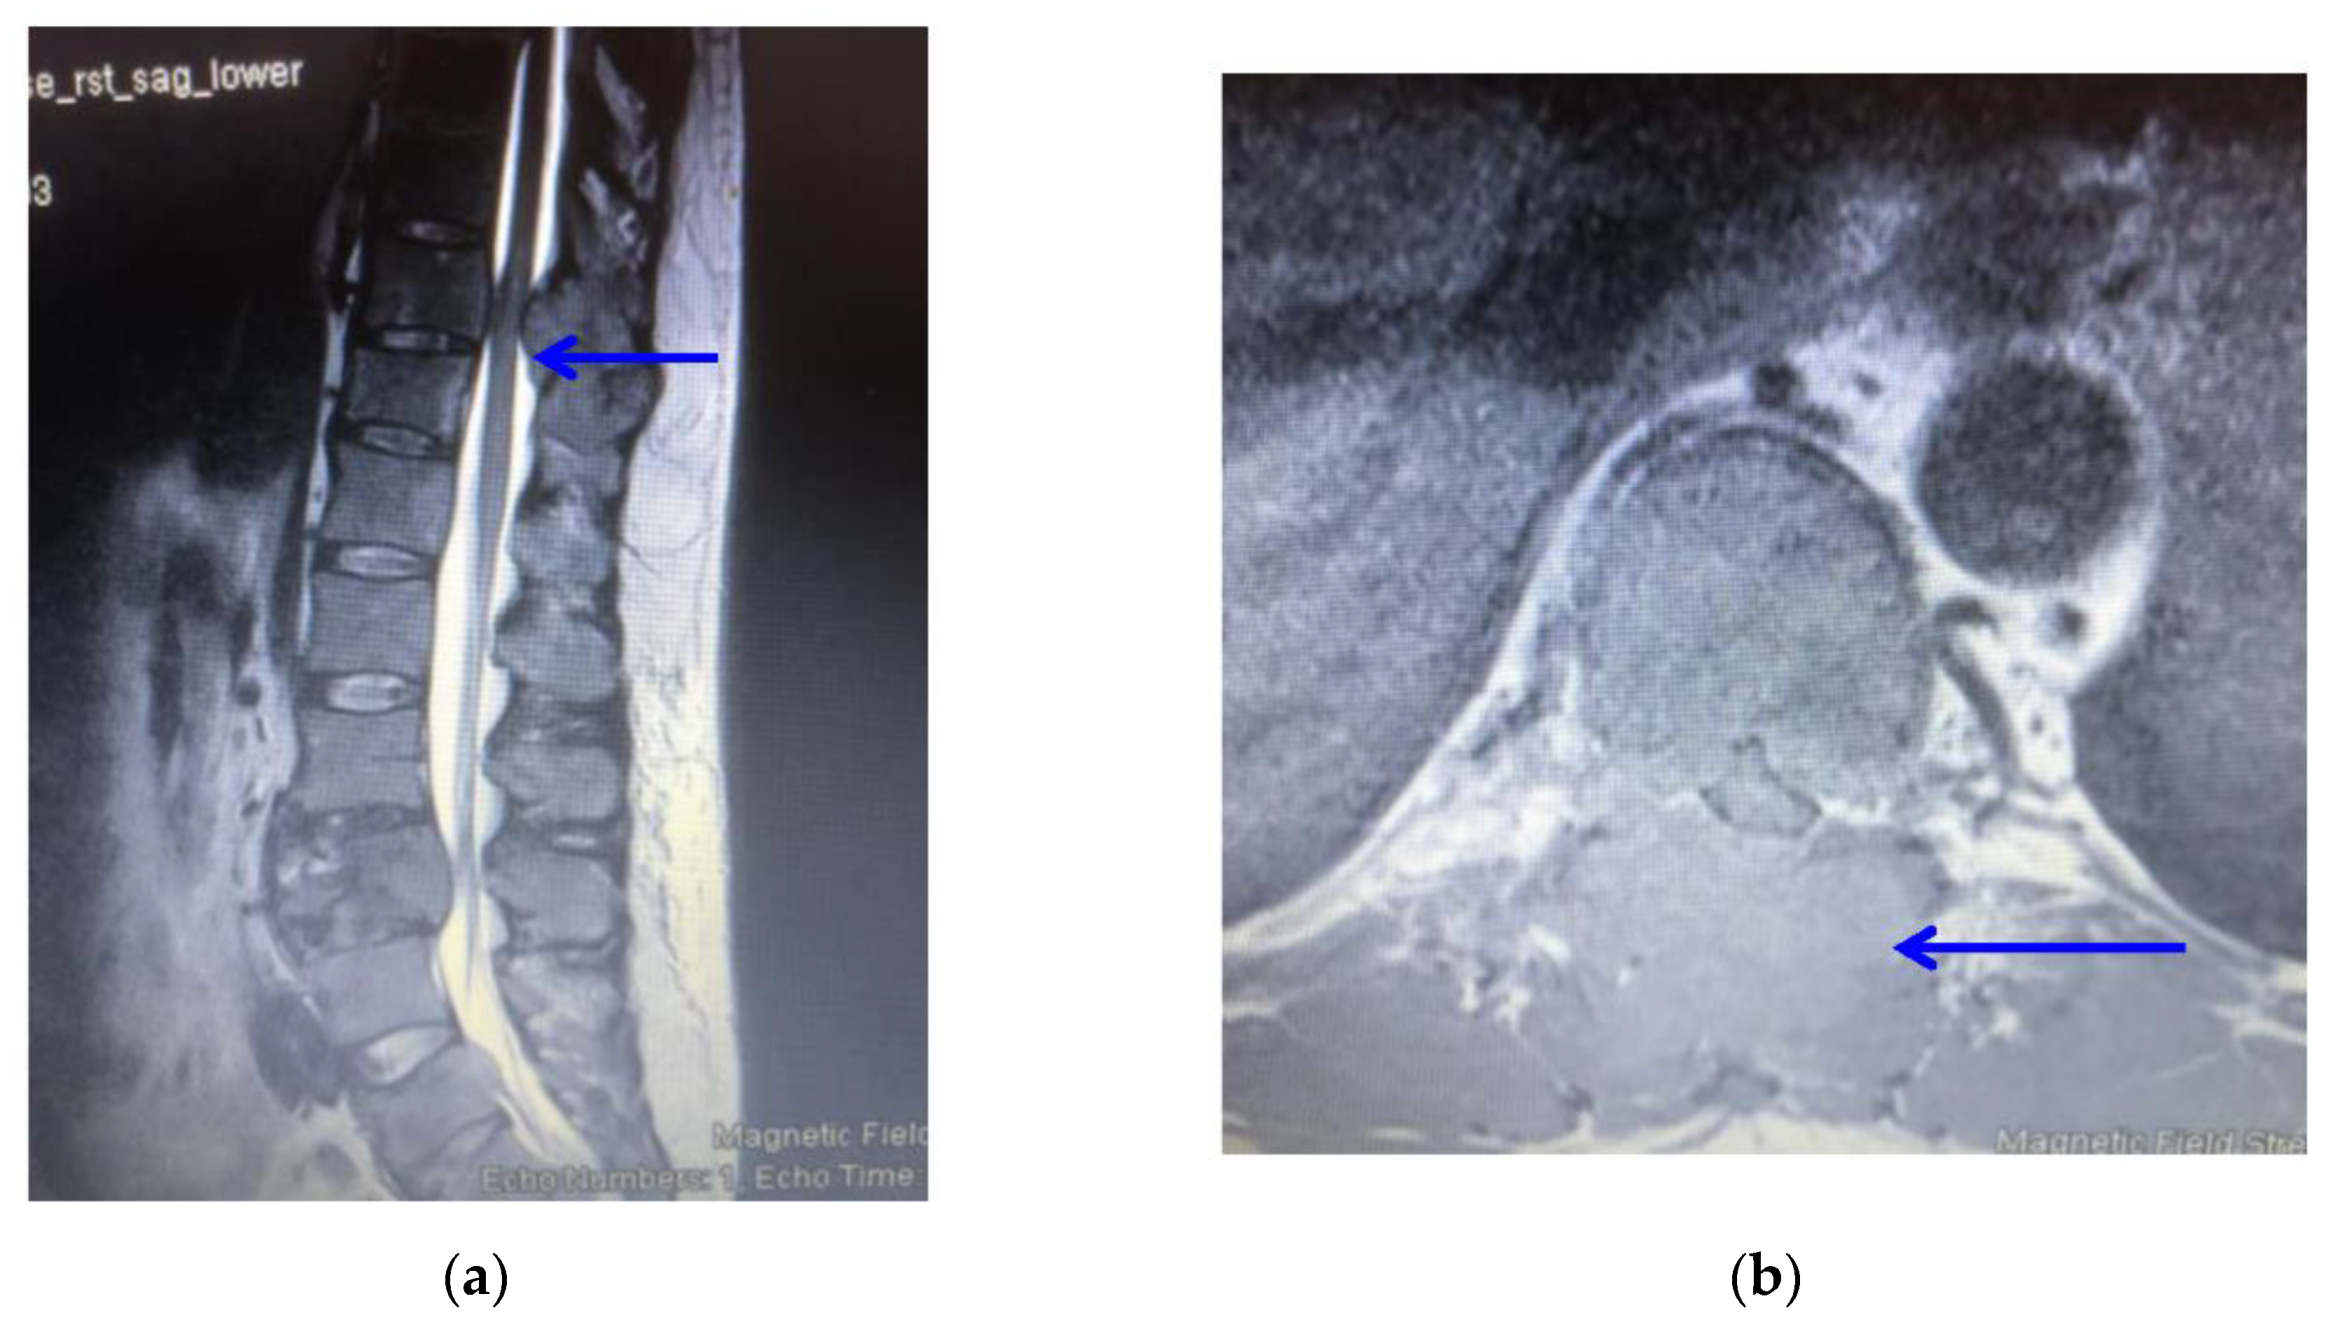

2. Case Report